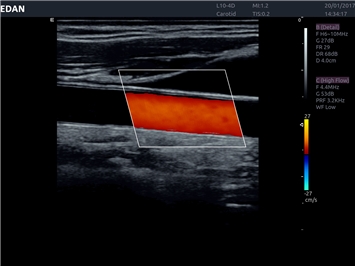

EDAN Acclarix LX4

Расширьте свои представления. Использование усовершенствованной платформой Acclarix система LX4 обеспечивает непревзойденную четкость изображений и интеллектуальный рабочий процесс для всех пользователей, являясь при этом наиболее экономичным решением.

EDAN Acclarix LX4 представляет собой инновационную ультразвуковую систему, построенную на усовершенствованной платформе Acclarix. Сочетание высокого качества визуализации с интеллектуальным рабочим процессом делает эту систему оптимальным выбором для клиник, ценящих эффективность и экономичность.

• Автоматическое измерение толщины интима-медиа

• Сосудистой диагностики

Недопплеровская визуализация кровотока:

Да